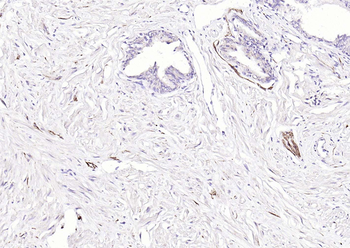

CD56 Antibody

Catalog Number: orb1317086

| Tested applications | IHC, WB |

| Reactivity | Human, Mouse, Rat |

| Dilution range | WB 1:2000, IHC 1:150 |